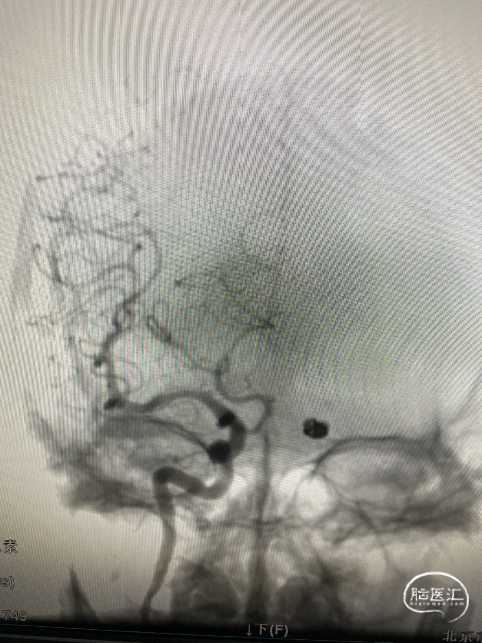

工作位+路图下Synchro-0.014in×200cm微导丝携带PROWLER SELECT PLUS微导管送至右侧大脑中动脉M2段远端,微导丝携带Echelon-10微导管送至M1段动脉瘤体内。经PROWLER SELECT PLUS微导管释放ENTERPRISE2 4.0mm×16mm,覆盖瘤颈,经Echelon依次填入强生ORBIT GALAXY 3mm×6cm弹簧圈成篮,继续填入ev3 2.5mm×6cm,1mm×2cm,1mm×1cm弹簧圈,造影示M1段动脉瘤填塞完全,造影剂滞留。

调整工作位角度,路图下Synchro0.014×200cmm微导丝携带SL-10微导管送至右侧颈内动脉,再用微导丝携带Echelon-10微导管送至C7动脉瘤瘤体内,经Echelon-10半释放强生ORBIT GALAXY 3mm×8cm弹簧圈,经SL-10释放Neuroform Altas 4.0mm×21mm支架,覆盖瘤颈,继续填塞第一枚弹簧圈,造影示支架位置满意,继续填塞强生ORBIT GALAXY 2mm×6cm弹簧圈,ev3 1mm×3cm,1mm×2cm弹簧圈,复查造影示动脉瘤栓塞致密,载瘤动脉通畅,复查颅内正侧位造影右侧颈内动脉、大脑前动脉、大脑中动脉显影良好。

复查:左侧颈内动脉C7段动脉瘤完全栓塞

经PROWLER SELECT PLUS微导管释放ENTERPRISE2 4.0mm×16mm,覆盖瘤颈,经Echelon依次填入强生ORBIT GALAXY 3mm×6cm弹簧圈成篮,继续填入ev3 2.5mm×6cm,1mm×2cm,1mm×1cm弹簧圈,造影示M1段动脉瘤填塞完全,造影剂滞留。

路图下Synchro0.014×200cmm微导丝携带SL-10微导管送至右侧颈内动脉,再用微导丝携带Echelon-10微导管送至C7动脉瘤瘤体内,经Echelon-10半释放强生ORBIT GALAXY 3mm×8cm弹簧圈,经SL-10释放Neuroform Altas 4.0mm×21mm支架,覆盖瘤颈。

造影示支架位置满意,继续填塞强生ORBIT GALAXY 2mm×6cm弹簧圈,ev3 1mm×3cm,1mm×2cm弹簧圈,复查造影示动脉瘤栓塞致密,载瘤动脉通畅。

造影右侧颈内动脉、大脑前动脉、大脑中动脉显影良好。